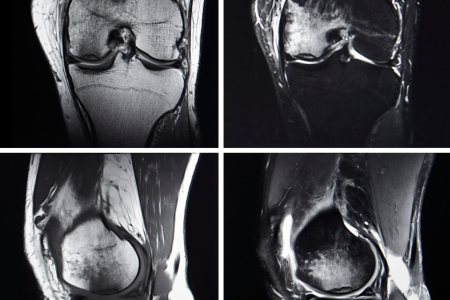

一方、MRI検査は、骨だけでなく、軟骨や靭帯、半月板といった軟部組織の状態を詳しく調べることができます。レントゲン検査では見ることができない、軟骨のすり減りや損傷、半月板の損傷なども、MRI検査では見つけることができるのです。

一方、MRI検査は、強力な磁場と電波を使って体の内部を画像化します。そのため、レントゲンでは見えない軟骨や靭帯、半月板の状態まで詳しく調べることができるのです。

レントゲン検査で見つけることが難しい、軟骨のすり減り具合や損傷の程度、半月板の損傷なども、MRI検査なら見つけることができます。また、骨の中の炎症なども確認できるため、より詳細な情報を得ることが可能です。